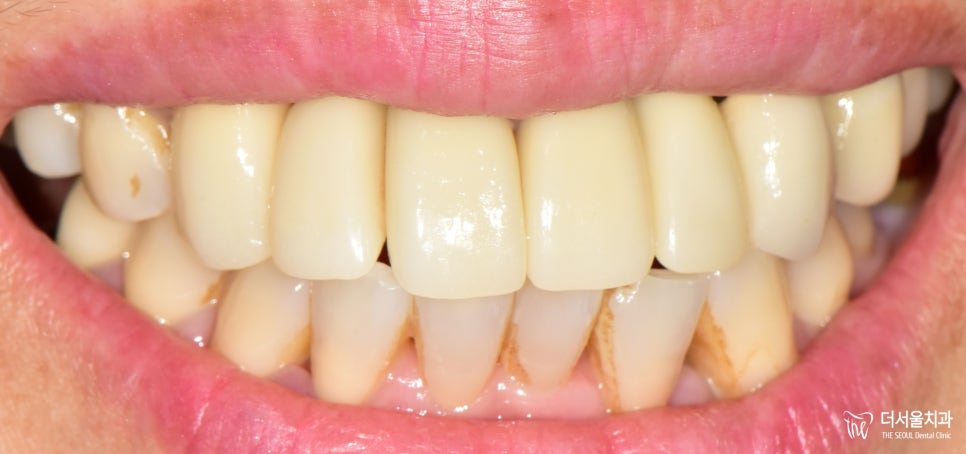

그렇게 컴퓨터 분석을 이용한

계획 수립으로 앞니 부러짐은

임플란트 보철 식립으로 잘 해결되었습니다.

거의 티가 나지 않게끔

크라운 제작 및 세팅에 힘을 썼습니다.

환자분 또한 깔끔하며

좋은 결과를 얻게 되어 너무 좋다고,

꼼꼼히 잘해주셔서 감사하다고 말씀하셨습니다.